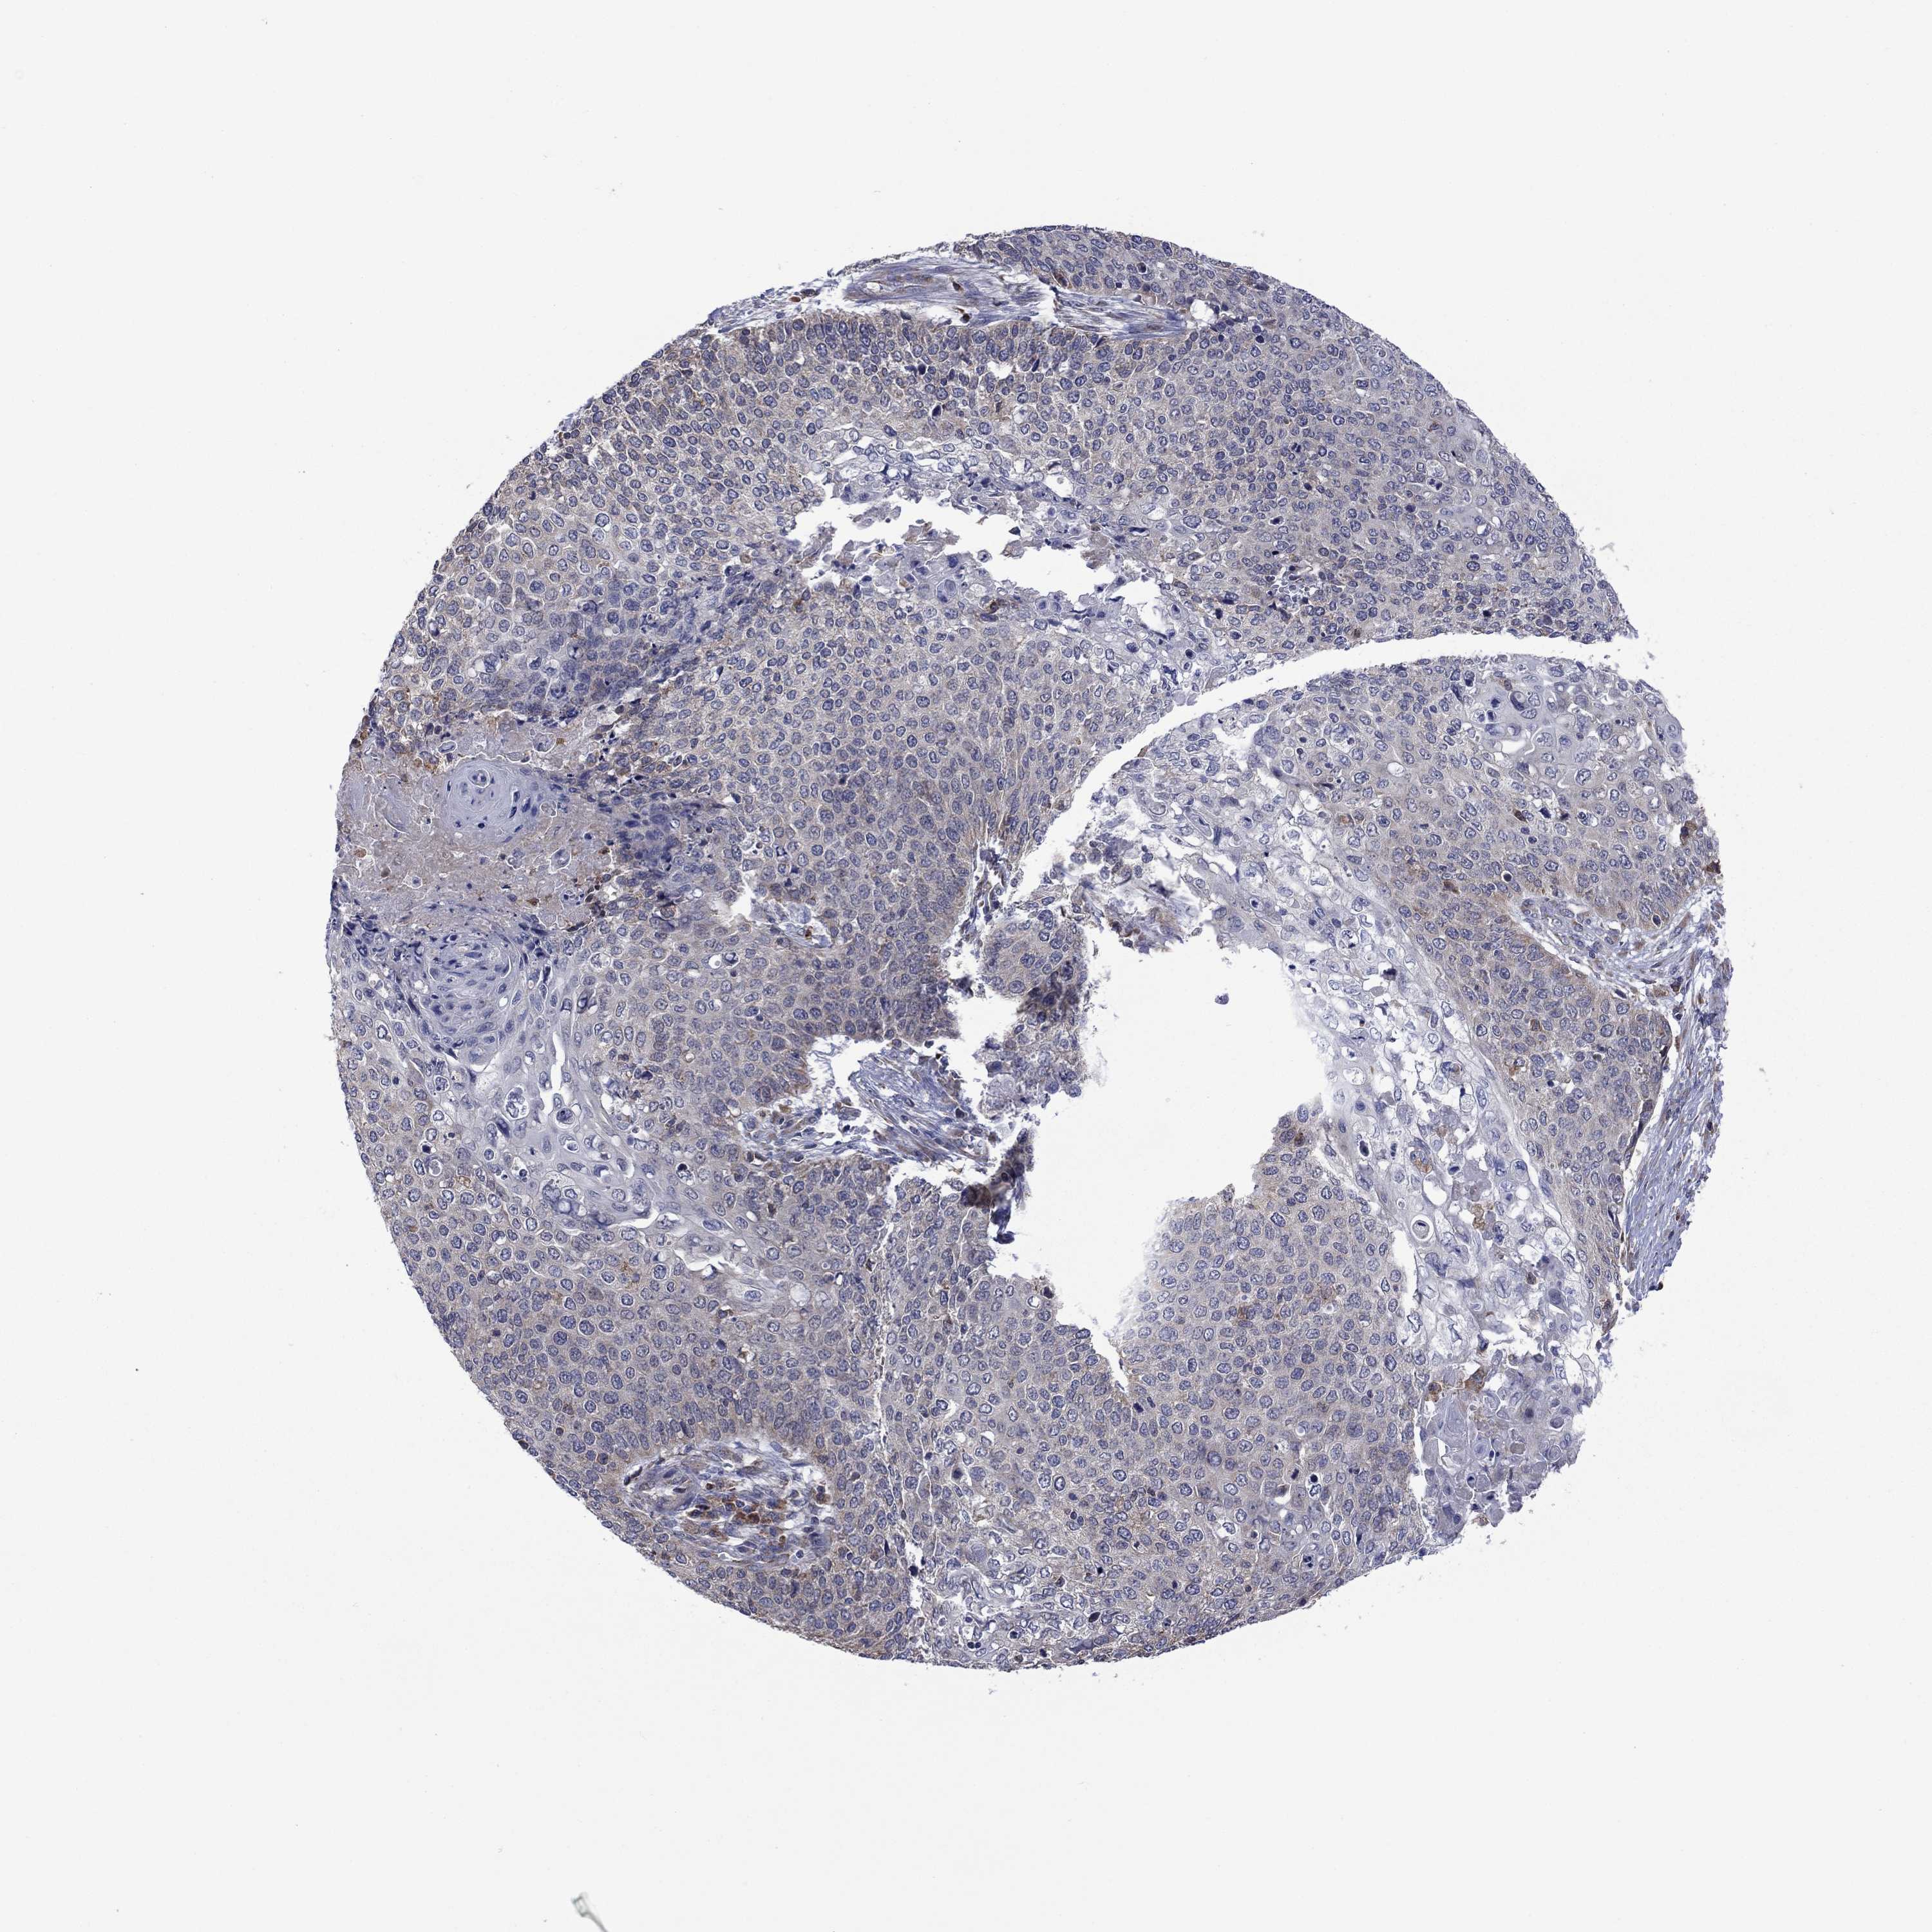

CERVICAL CANCER - Protein expressioni

A mouse-over function shows sample information and annotation data. Click on an image to view it in a full screen mode. Samples can be filtered based on level of antibody staining by selecting one or several of the following categories: high, medium, low and not detected. The assay and annotation is described here.

Note that samples used for immunohistochemistry by the Human Protein Atlas do not correspond to samples in the TCGA dataset.

Antibody stainingi

Antibody staining in the annotated cell types in the current human tissue is reported as not detected, low, medium, or high, based on conventional immunohistochemistry profiling in selected tissues. This score is based on the combination of the staining intensity and fraction of stained cells.

Each image is clickable and will lead to virtual microscopy that enables deeper exploration of all samples and also displays staining intensity scores, fraction scores and subcellular localization as well as patient and tissue information for each sample.

Antibody CAB009499

Adenocarcinoma, NOS